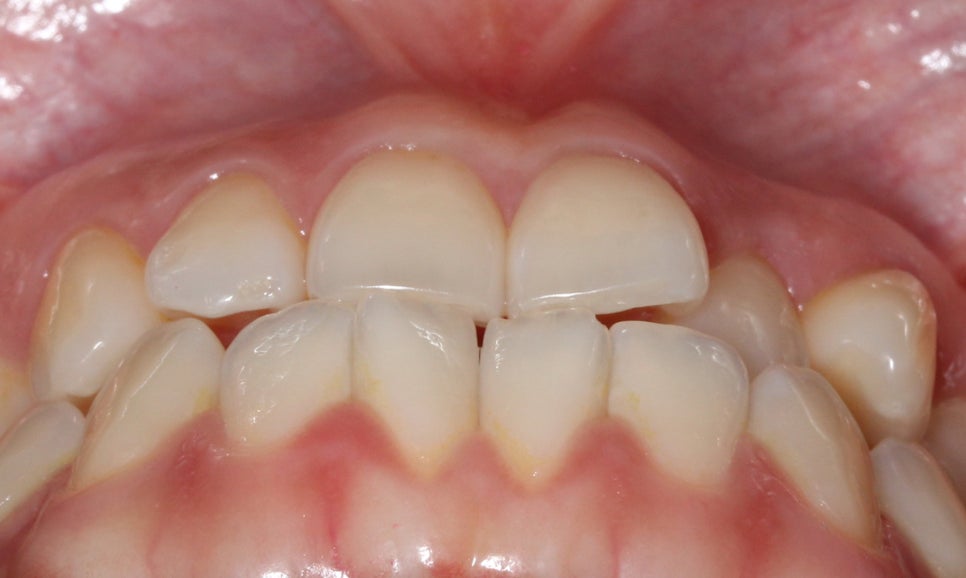

절단교합 교정 전 교합평면을 보면

상악과 하악의 교합 상태를 정확히

파악할 수 있습니다.

상악 교합면 사진입니다.

사진에서 우측 측절치가 설측으로

들어와 있어서 전치부

치열이 삐뚤거리는 모습인데요,

이러한 경우 들어와 있는 측절치를

원래 위치로 빼내기 위해서

주변 치아들을 이동시켜 공간을 만들어 주어야 합니다.

교정 초기에 이 부분에 open coil spring이

(공간확보 용)결찰될 수 있습니다.

하악 교합면은 위처럼 앞쪽의 중절치가

마주 보듯이 회전되어 있는 모습으로

최후방의 어금니(사랑니)를 발치하여

공간을 확보할 예정입니다.